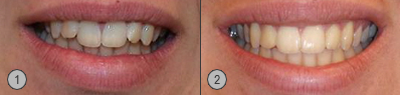

Informationen über die Korrektur vom "Deckbiss" anhand einem Patientenbeispiel mit einer Twin-Block Kombibehandlung mit Invisalign®.

- Vor Deckbiss Korrektur

- Nach Deckbiss Korrektur

Patientenbilder Vor-, und Nach der Korrektur mit Twin Block

patientenbeispiel mit vorher und nachher Bilder der Deckbiss Korrektur